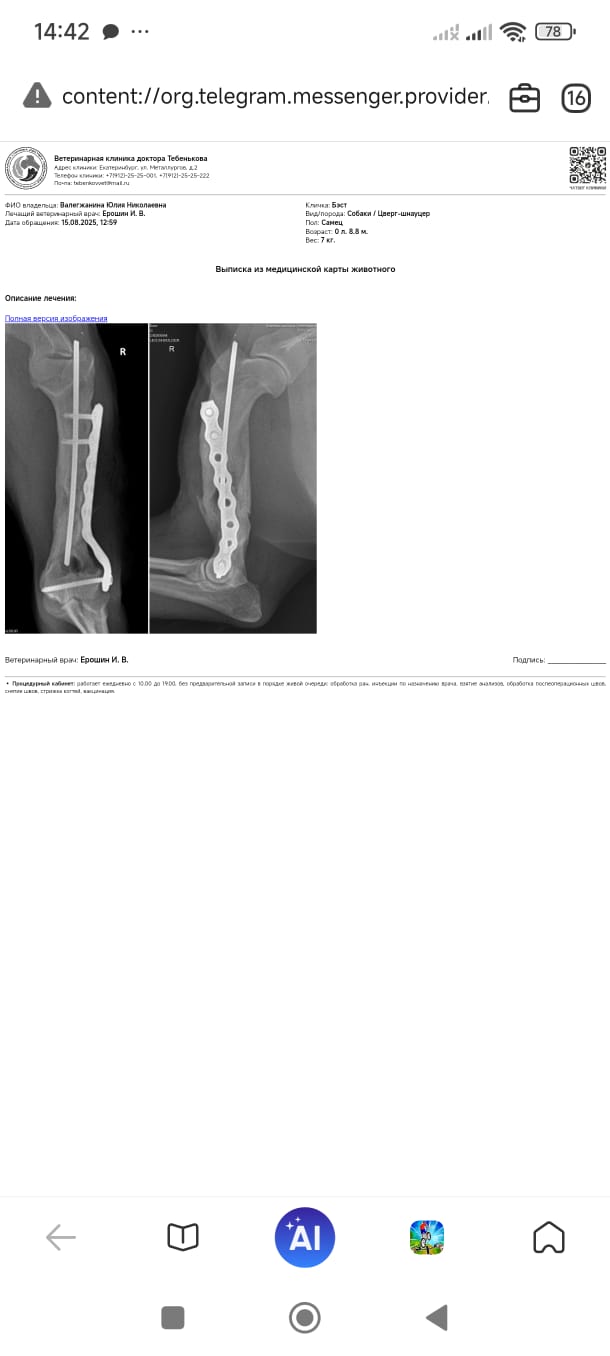

Лиза отвезла зверя к ортопеду на ещё одну консультацию.

Он сказал, что перелом несвежий, недели 2.

Возраст месяцев 8.

Сегодня оставили на операцию, поставят пластину, а завтра домой. Еще я попросила лишние зубы заодно вынуть.

Операцию сделали, завтра утром выдадут обратно.

Лапу надо беречь, прыжки исключать, поверхности не скользкие, нагрузки избегать.

Через 10 дней снимать швы, через полтора месяца контроль.

Доктор сказал, что такие старые оскольчатые переломы плохо срастаются.

Бэста выдали из клиники, операцию сделали, швы снимать через 10-12 дней и контрольный рентген через полтора месяца.

Вчера Бэст ездил к врачу.

Выписка в регистратуре, все идет по плану, через 6 недель контрольный рентген.

2. Бэсту потихоньку снимают винты с лапы.